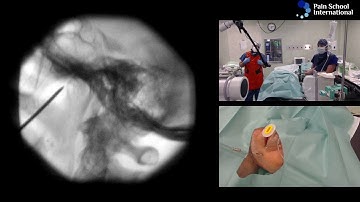

Gasserian ganglion Trigeminal block - made simplified by demo on the skull